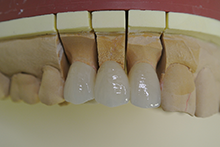

オールセラミックス

金属を使わずに全てセラミックを使用し、光の透過性を上げる事により自然な白い歯に回復させる方法です。

現在では土台から白い材質(ファイバーポストなど)の物を使用することにより、さらに透明感が増し天然歯に近似しています。

オールセラミックは近年進化を遂げており、強度や接着性がかなり改善され、審美的にとても優れたものと成って来ております。

オールセラミックにも色んな種類がありますが、当院ではe-max(二ケイ酸リチウムガラスセラミック、)ジルコニアセラミックスを採用しています。